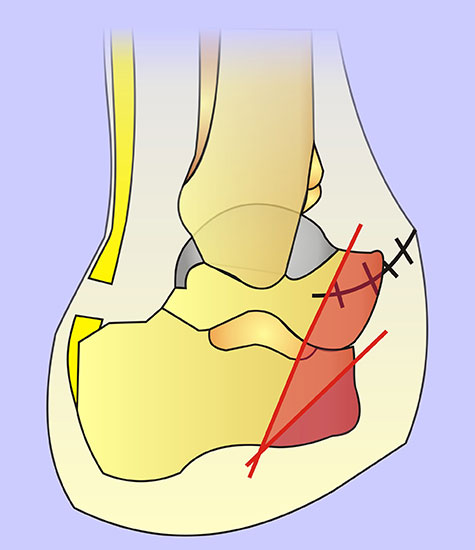

Wird der Ansatz des M. fibularis (peroneus) brevis bei Amputation des 5. Strahls entfernt, kommt es durch das muskuläre Ungleichgewicht zu einer Supination mit Vorfußadduktion und nachfolgend zu einer vermehrten Druckbelastung am Außenrand des Fußes (Abb. 30, 31). Um einer chronischen Ulzeration vorzubeugen, muss die Fehlstellung beseitigt werden, meist durch Transfer der Tibialis anterior Sehne.

Wird der Ansatz der Sehne des M. fibularis brevis bei erhaltenem Tibialis anterior entfernt, resultieren aufgrund des muskulären Ungleichgewichts eine Adduktion und eine Supination. Dies führt zur Ulzerationen am Fußaußenrand. Wenn der Ansatz der Sehne des M. tibialis anterior (bei Erhalt der Fibularis brevis) entfernt wird, resultiert eine Abduktion, Pronation und Equinus-Stellung. Sollte die Entfernung der Sehnenansätze unvermeidbar sein, müssen Lösungen zum Ersatz gefunden werden: z.B. durch Sehnentransposition oder korrigierende Arthrodesen.

Auf dem Niveau der Tarso-metatarsal-Gelenke (TMTG) kommen die operationstechnischen Prinzipien der TMA analog zur Anwendung (Abb. 41). Nach Absetzen in der Gelenkreihe werden die Knochenkanten nach medial, plantar und lateral abgeschrägt. Wesentlich ist, dass bei einer Amputation in der Lisfranc-Gelenklinie die Sehnenansätze des M. fibularis (peroneus) brevis immer und die Sehne des M. tibialis anterior häufig entfernt. Um eine Spitzfußstellung bzw. störende Seitdeviation zu umgehen, sollte nach Möglichkeit eine Resinsertion vorgenommen werden. Alternativen sind eine Durchtrennung der Achilles- und Tibialis-posterior-Sehne mit einer Sehnentransposition.